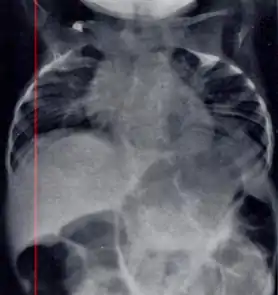

Radiograph depicting typical skeletal features of Jarcho-Levin syndrome, subtype spondylothoracic dysplasia. Note fanlike configuration of the ribs, with extensive posterior fusion, along with multiple vertebral segmentation defects.

Spondylothoracic dysplasia

Spondylothoracic dysplasia, or STD, has been repeatedly described as an autosomal recessively inherited condition that results in a characteristic fan-like configuration of the ribs with minimal intrinsic rib anomalies. Infants born with this condition typically died early in life due to recurrent respiratory infections and pneumonia due to their restricted thorax.[3][4][5] Recently, a report[6] has documented that actual mortality associated with STD is only about 50%, with many survivors leading healthy, independent lives.